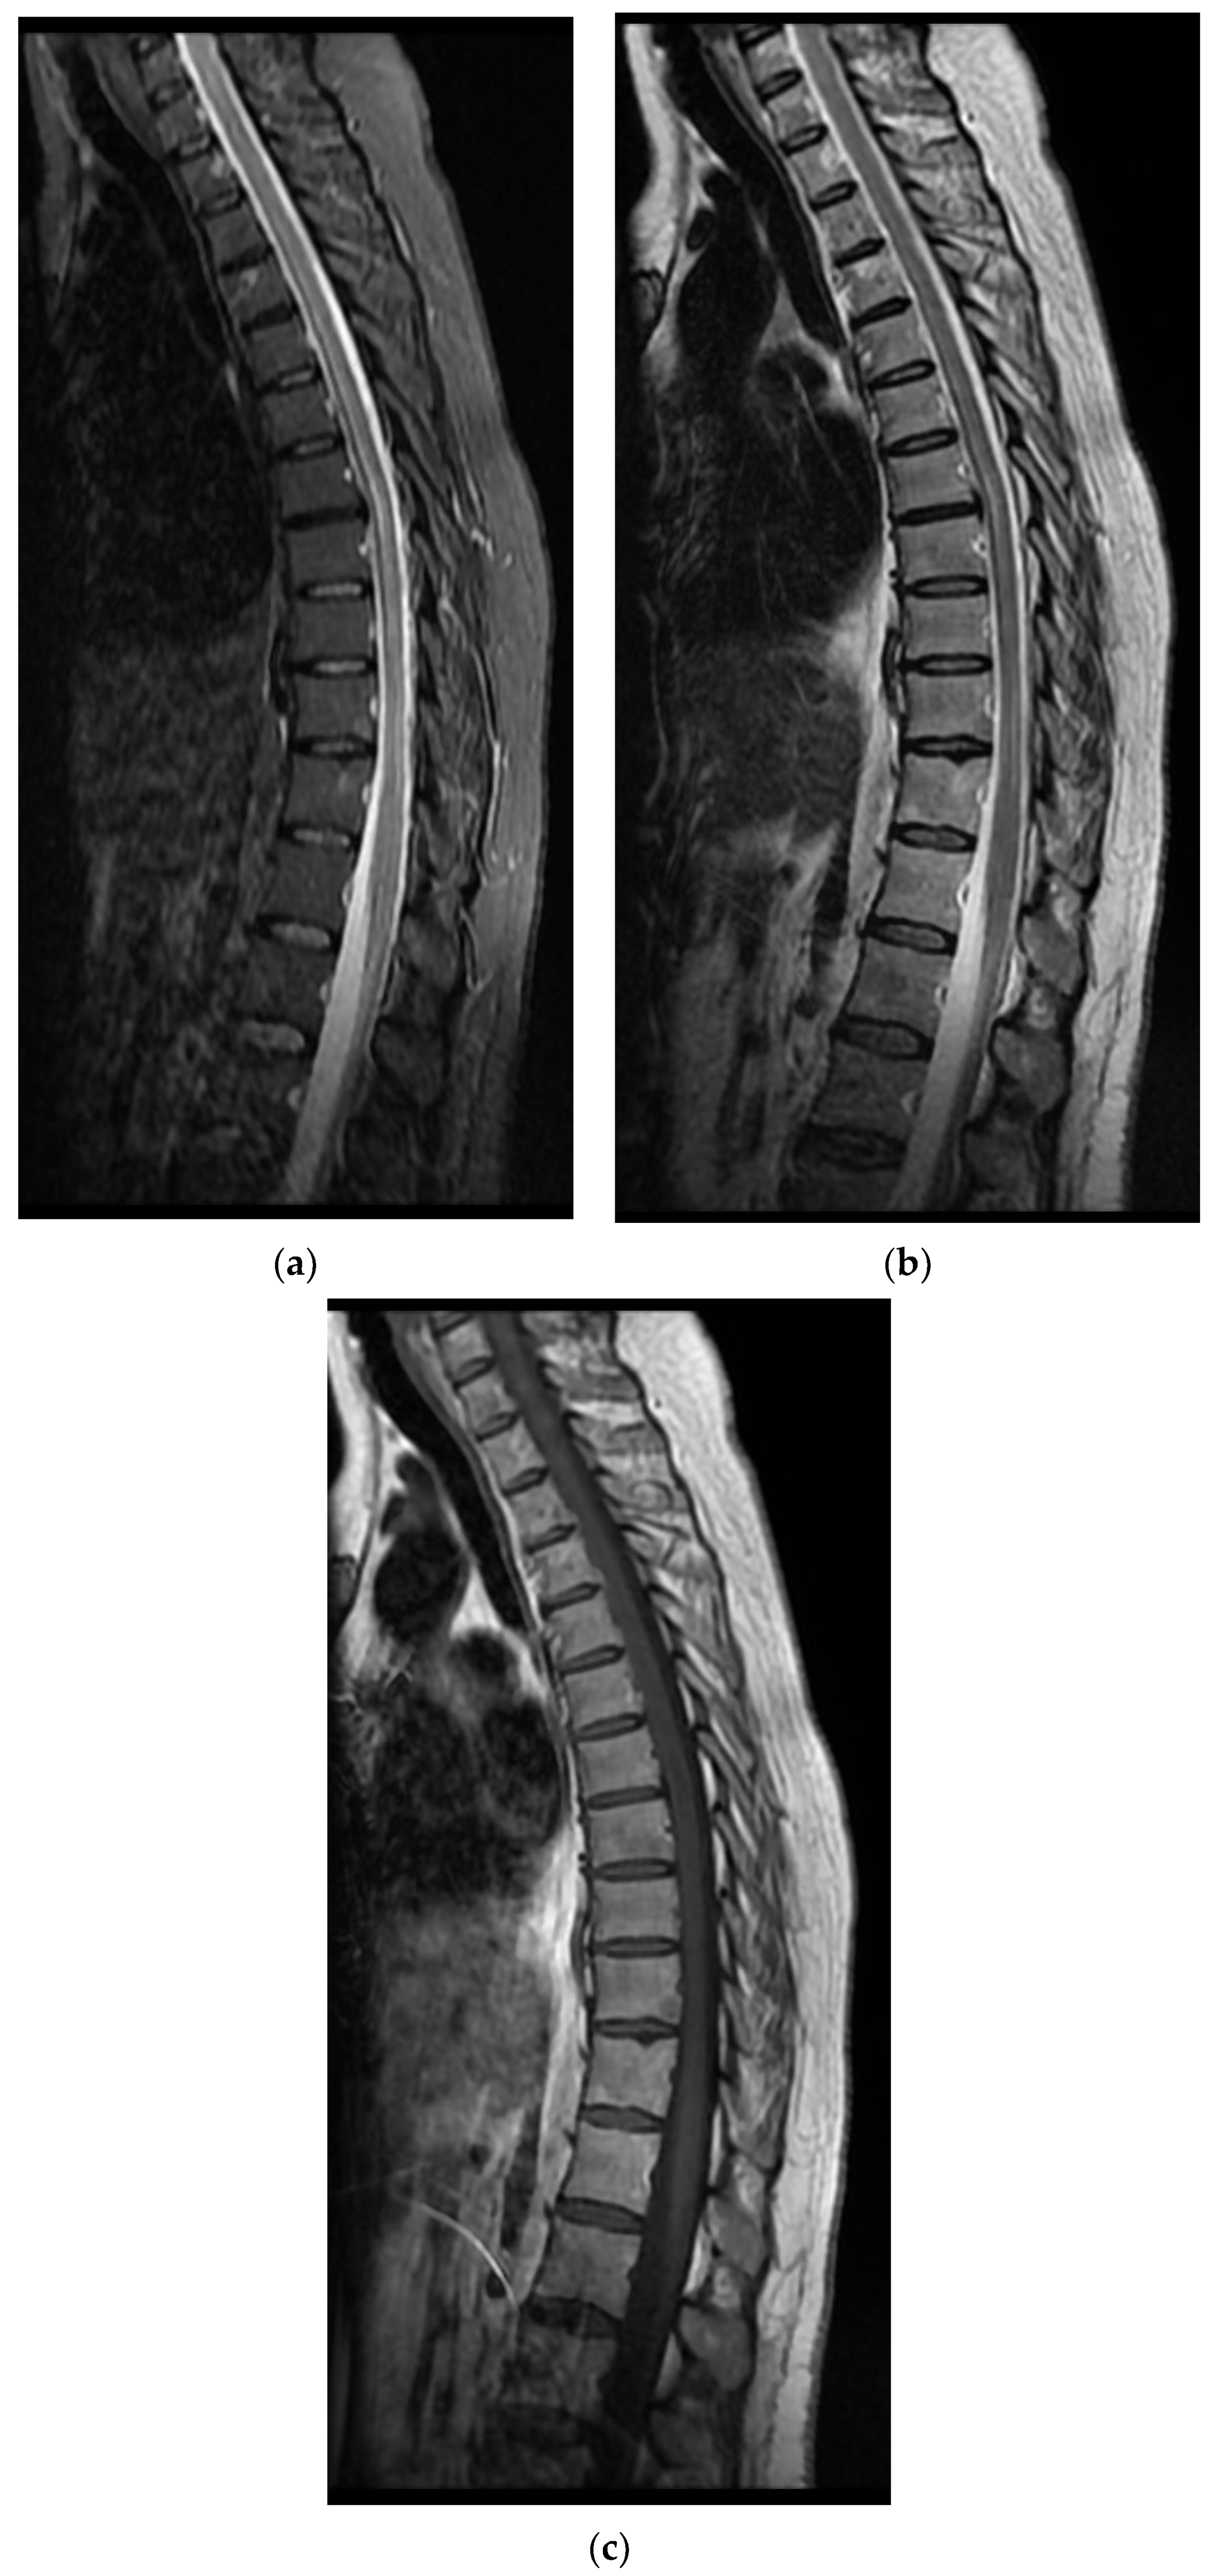

On the first day of hospitalization, when tested for SARS-CoV-2 RNA by RT-PCR, the result was positive. On the same day of hospitalization, the patient underwent a lumbar puncture (element count 155/mm3, albumin 310 mg/L, chlorine 128 mmol/L, and glucose 70 mg/dL) and a thoracolumbar spine MRI, which revealed thoracic intramedullary lesions suggestive of an inflammatory-infectious substrate (Figure 1).

Figure 1. MRI images of the Case 1 patient show inaccurate delimited discrete hyperintense foreshores T2-STIR (a,b), hypointense T1 (c), disposed at the level of lateral coordinates of the marrow corresponding to T6–T10 myeloma; thoracic intramedullary lesions with suggestive characters for an inflammatory-infectious sublayer.